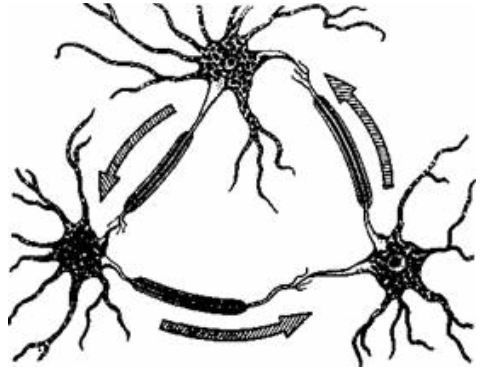

Физиология памяти: Механизмы и исследования